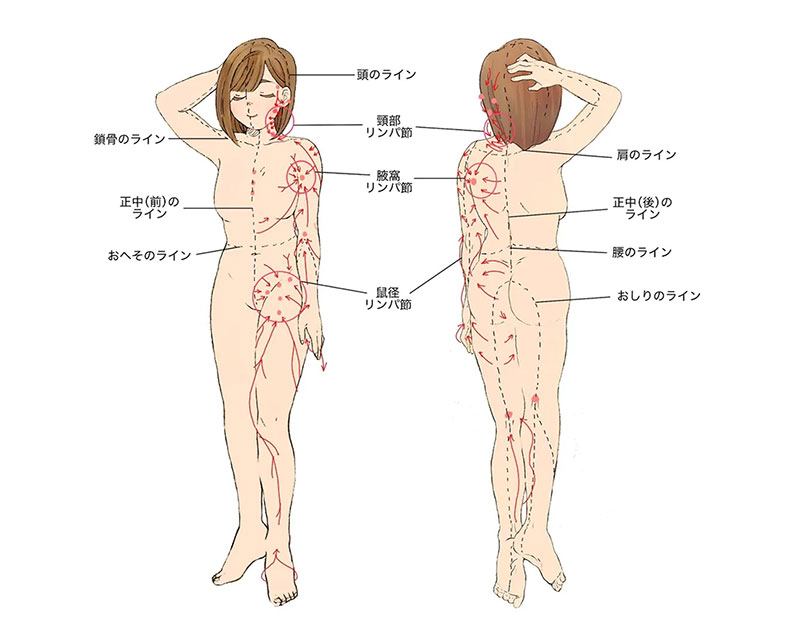

リンパ管は、主に皮下脂肪の中にある細い表在リンパ管と、頸部・腋窩部(わきの下)・鼠径部(足の付け根)にあるリンパ節、腹腔や胸腔から首まで達する深部リンパ管があります。

表在リンパ管は全身の皮下組織にきめ細かく張り巡らされていますが、その流れには体液区分線という境界線があり、それに従ってどのリンパ節に流れ込むかがが決まっています。体液区分線は、身体の中央、鎖骨へその上下などにあります。

リンパには体液区分線が存在するため手術を受けた部位によって発症する場所が変わり、乳がんの手術後は手術側の腕、骨盤内の手術後ではどちらかの足、または両足に発症します。